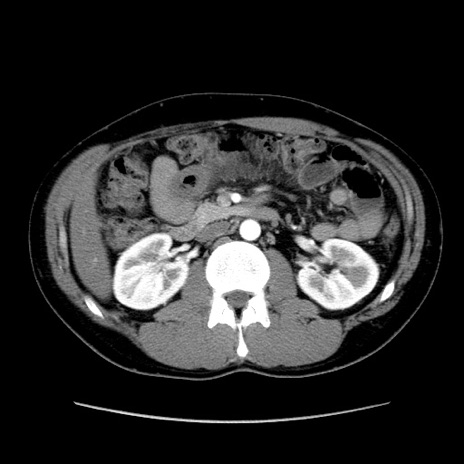

症例36(横断像)

【症例】20歳代 男性

【主訴】心窩部痛

【現病歴】今朝より上腹部痛あり。一旦軽快していたが再度出現したため救急要請。昨日夕に白身の魚を含む刺身を食べた。

【身体所見】BP 136/89mmHg、HR 74/min、BT 37.0℃、腹部:膨満、軟、心窩部に圧痛あり。反跳痛なし、筋性防御なし、腸雑音やや亢進あり。

【データ】WBC 17700、CRP 0.48